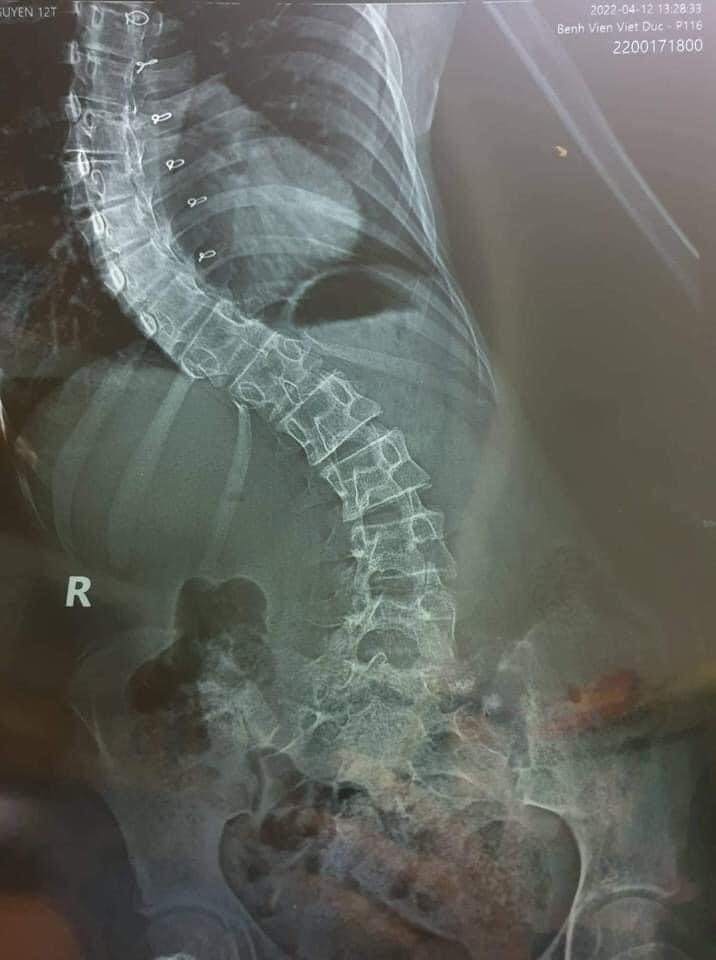

🍀 Gia cảnh : Mẹ sức khỏe yếu, không có công việc ổn định, bố mất, bản thân em bị tim bẩm sinh và cong vẹo cột sống. Bản thân là học sinh nghèo vượt khó, mắc bệnh hiểm nghèo phải dùng thuốc hàng ngày, khám định kỳ thường xuyên, không tự đi học được.